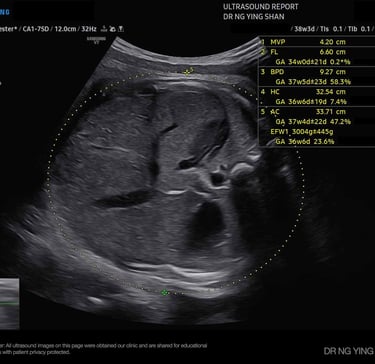

from 24

weeks onwards

Growth Scans

Monitors the baby’s size, fluid levels, and placenta health, especially if there are concerns about growth or complications.